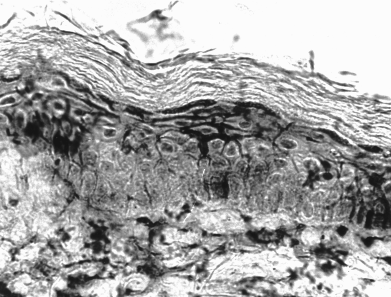

- Именно, Кошевенко Ю. Н. в 1972 году первым в отечественной дерматологии поставил реакции тканевой иммунофлюоресценции РИФ Coons (и прямую, и непрямую), более того получил препараты самые лучшие из существовавших! Вот они:

Таких качественных и показательных микропрепаратов при красной волчанке не получал больше никто — ни в СССР, ни за рубежом. Почему? Да потому, что Ю. Н. делал в микротоме-криостате срезы тканей толщиной всего 4 микрона (тогда как все остальные — 10-15 микрон). Делал с помощью надеваемого на нож своего «Приспособления для снятия срезов», оформленного как рац.предложение № 14.